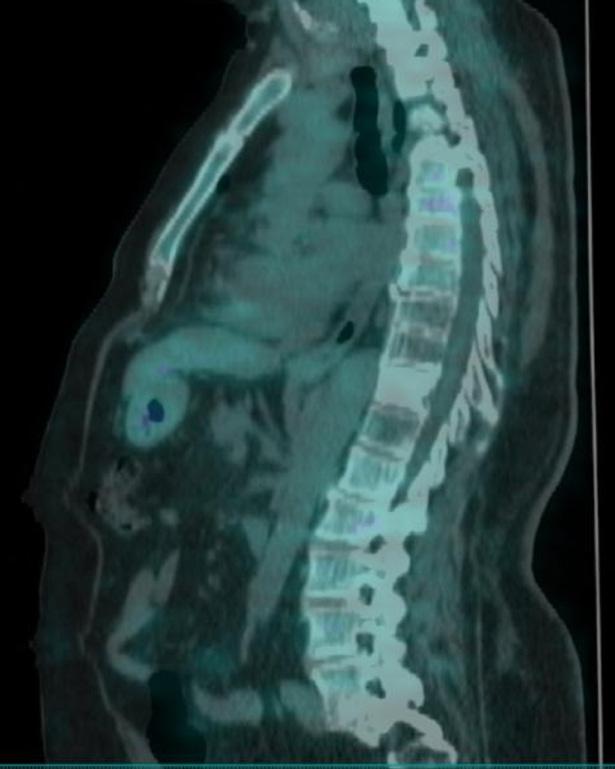

In seguito ad ulteriore progressione scheletrica riscontrata nel mese di Agosto 2022 (figura 5) la paziente ha pertanto avviato una seconda linea di trattamento con T-DXd 5,3 mg/kg nell’ambito del programma a uso nominale, ottenendo una risposta completa di malattia alla PET di Novembre 2022 (figura 6) dopo soli 3 cicli di trattamento. Dal 02/01/2023 prosegue a terapia ridotta al I livello 4,4 mg/kg per quadro di tossicità gastrointestinale con nausea G2, vomito, diarrea G2 e inappetenza. Dal secondo ciclo abbiamo potenziato la premedicazione antiemetica con desametasone per os per 3 giorni. Nonostante ciò la paziente ha riportato nausea G2 per i primi sette giorni dopo l’infusione e nausea G1 per i successivi 14 giorni. Da quando abbiamo ridotto la dose al I livello la paziente non lamenta alcun disturbo, in questo modo c’è stato un miglioramento dei sintomi, con conseguente prosecuzione della terapia con T-DXd senza interruzioni e con una ottima qualità della vita. Ottobre 2023 riscontro clinico di fini crepitii alle basi polmonari bilateralmente, no aree di ottusità alla percussione, parametri vitali nella norma. Si esegue HRTC, visita cardiologica con ecocardio e valutazione della FEVs ed indici di flogosi PCR e procalcitonina per escludere eziologia infettiva. La paziente nega disturbi, porta in visione gli indici di flogosi e visita cardiologica che risultano nella norma, la HRTC (figura 7) rileva la comparsa di ispessimenti interstiziali subpleurici bilateralmente; coesistono alterazioni a vetro smerigliato. La strategia intrapresa è stata quella di interrompere il trattamento con T-DXd ed iniziare una terapia con prednisolone 1 mg/kg per 20 giorni con graduale riduzione della dose e ripetizione della HRTC

Figura 5. PET Agosto 2022.